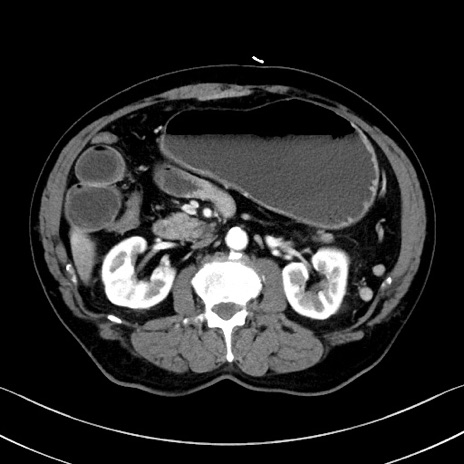

冠状断像

症例35(横断像)

【症例】70歳代 男性

【主訴】腹部膨満、嘔吐

【現病歴】昨日より腹部膨満感出現。本日増悪し、仙痛出現。嘔吐あり、受診。

【既往歴】糖尿病、胆摘後

【身体所見】BP 149/80mmHg、HR 74/min、BT 35.9℃、腹部:膨満、軟、圧痛なし。腸雑音減弱あり。上腹部正中切開瘢痕あり。

【データ】WBC 13500、CRP 1.72